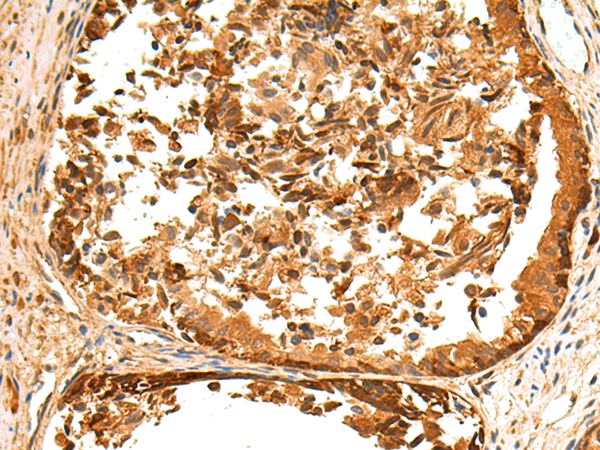

IHC positive control: |

Human tonsil and Human liver cancer; Human prostate cancer and Human gastric cancer |